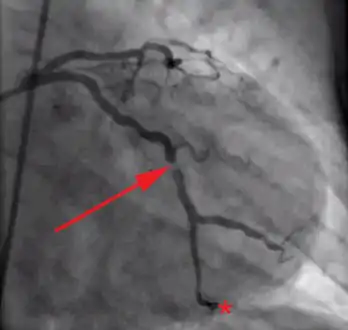

Angiographic image showing extensive LAD thrombosis

Coronary angiography of an MI patient